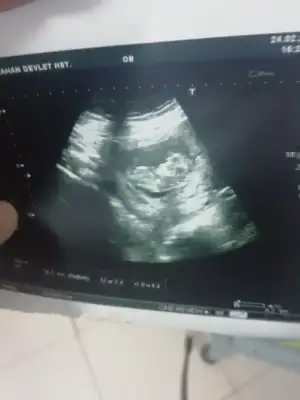

Kızlar dün doktora gitmiştim yine. Yeni kanama alanı gözükmüyor çok şükür.

İnşallah son olmuştur artık 🤲😅